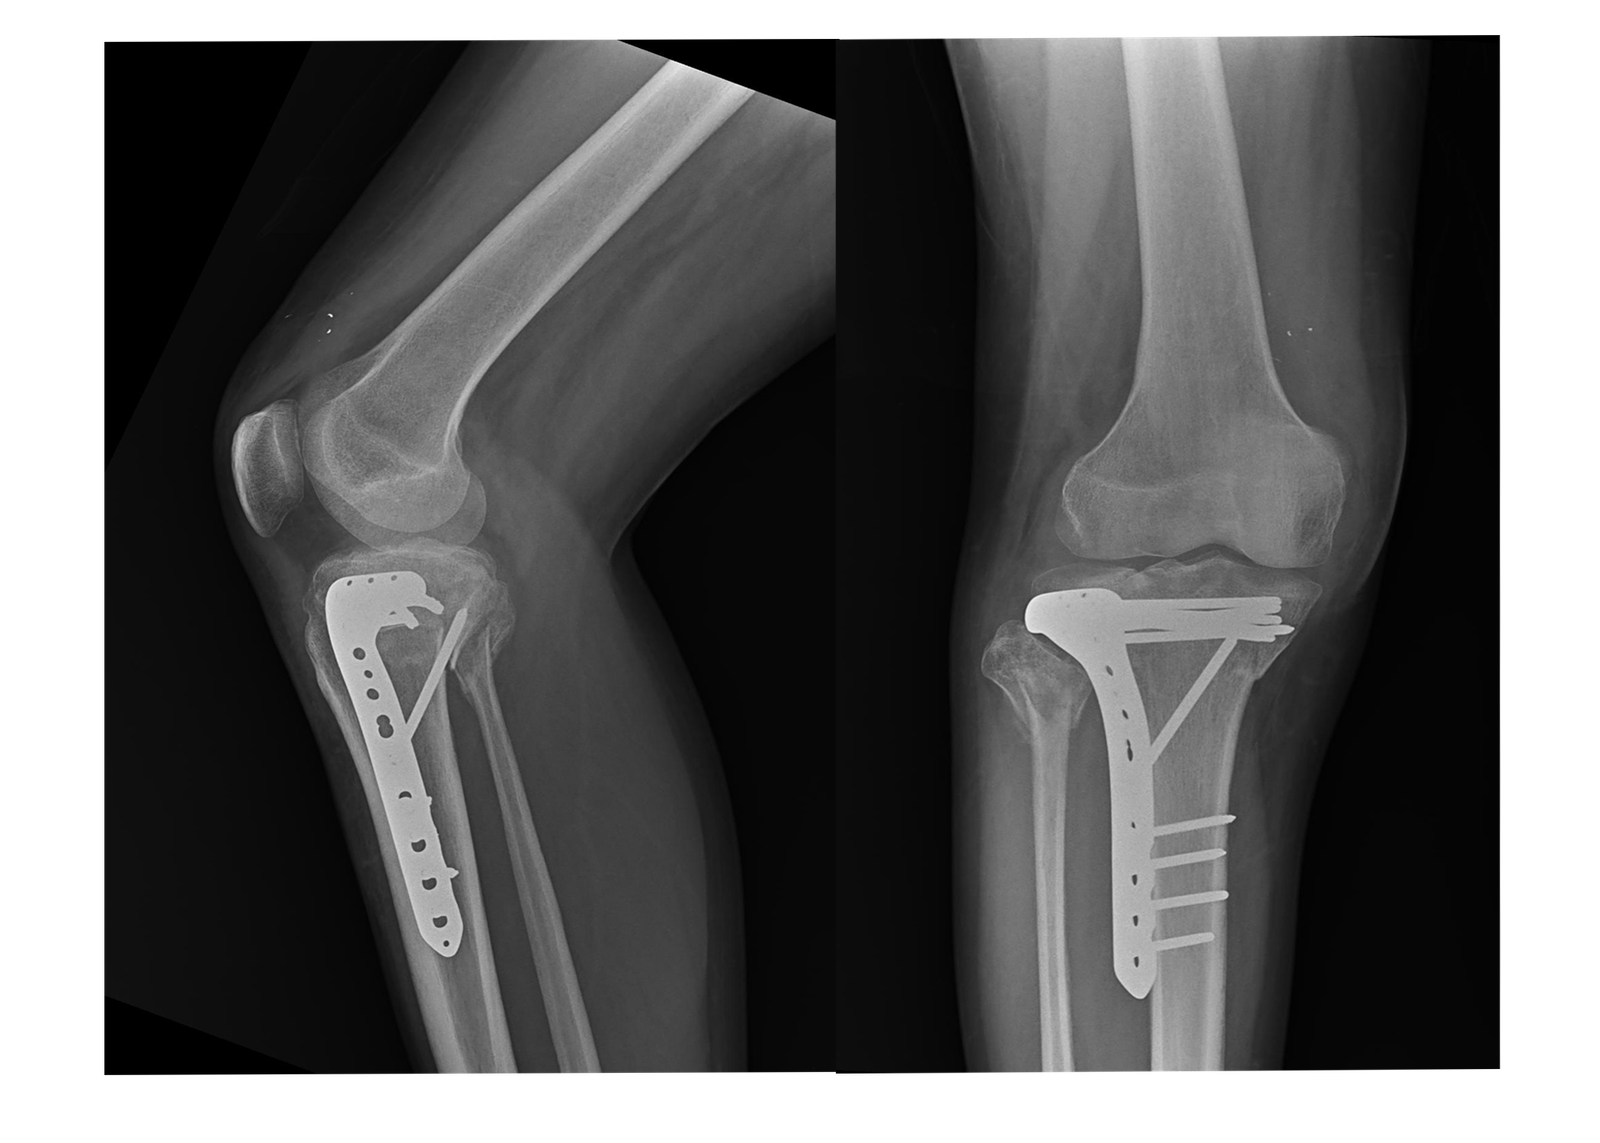

1. Total Knee Replacement (TKR):

Our Total Knee Replacement procedures are designed to relieve pain and restore function in patients suffering from severe arthritis or knee damage. Using advanced surgical techniques and high-quality prosthetic implants, we ensure that patients receive the best possible care and achieve optimal recovery.

4. Revision Joint Replacement:

We also specialize in revision joint replacement surgeries for patients who have previously undergone joint replacement but are experiencing complications or implant failures. Our expertise in this area allows us to offer effective solutions and restore joint function.

X-Rays